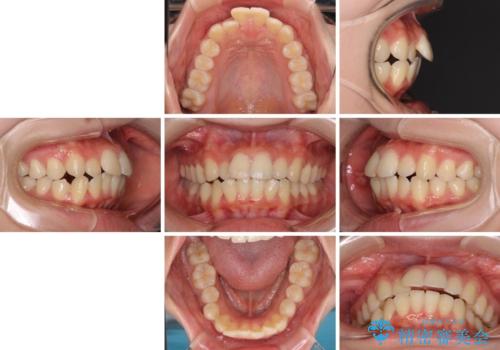

- 口元の閉じにくさを気にして来院された患者様です。

上下ともに歯列が前方に突出していたため、上下左右の第一小臼歯4本を抜去し、ワイヤー装置による矯正治療を行うこととしました。

舌の突出癖による影響もあったため、舌のトレーニングを並行して実施しました。

上下左右4本抜歯する場合には、通常2年から2年半ほどの期間を要しますが、僅か1年半で終了することができました。